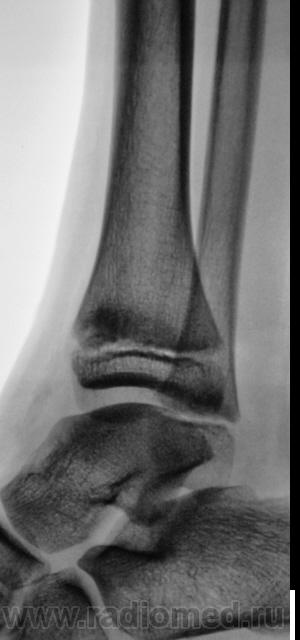

Уважаемый Валентин Львович! А что в жалобах, анамнезе? В переднемедиальной зоне дист. метафиза б/берцовой кости субхондрально под зоной роста участок уплотнения к/структуры, не отграниченный от неизмененной костн. ткани. Возможно, это импрессионный перелом? или остеонекроз? Смущает небольшой очаг аналогичной структуры в таранной кости под медиальным валом блока.

Клиника перелома. Травма - за 4 часа до исследования.

Согласен с коллегой helenmar по поводу перелома по типу импрессии, а ещё подвывих стопы в г/стопном суставе.

А как же объяснить асимметрию рентгеновской суставной щели?

А на мой взгляд, суставная щель вполне симметрична.

А, что, это за фрагментик?

У взрослого такие соотношения в суставе назову супинационным подвывихом, хотя прямая проекция не оптимальна для такого заключения, боковая вовсе косая.